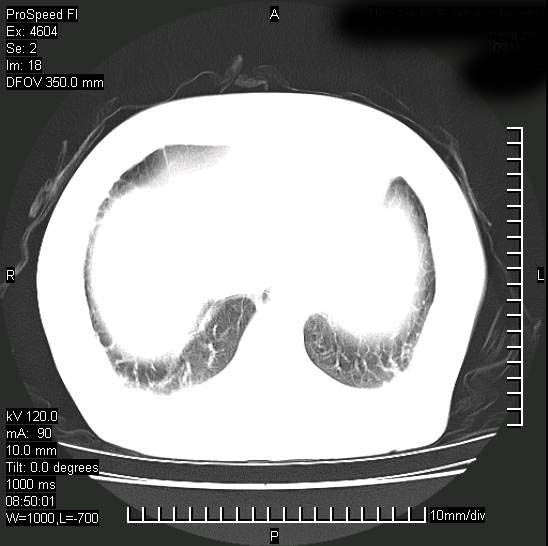

十几年前曾患肺结核,一周前突咳血约100ml,中性粒细胞稍高,诊断两上肺陈旧结核,下肺炎症,给予抗炎治疗,近几日晚上高热,39度,仍咳少量血,4天前ct及今天ct上传。

[face=黑体]8月30日[/face]